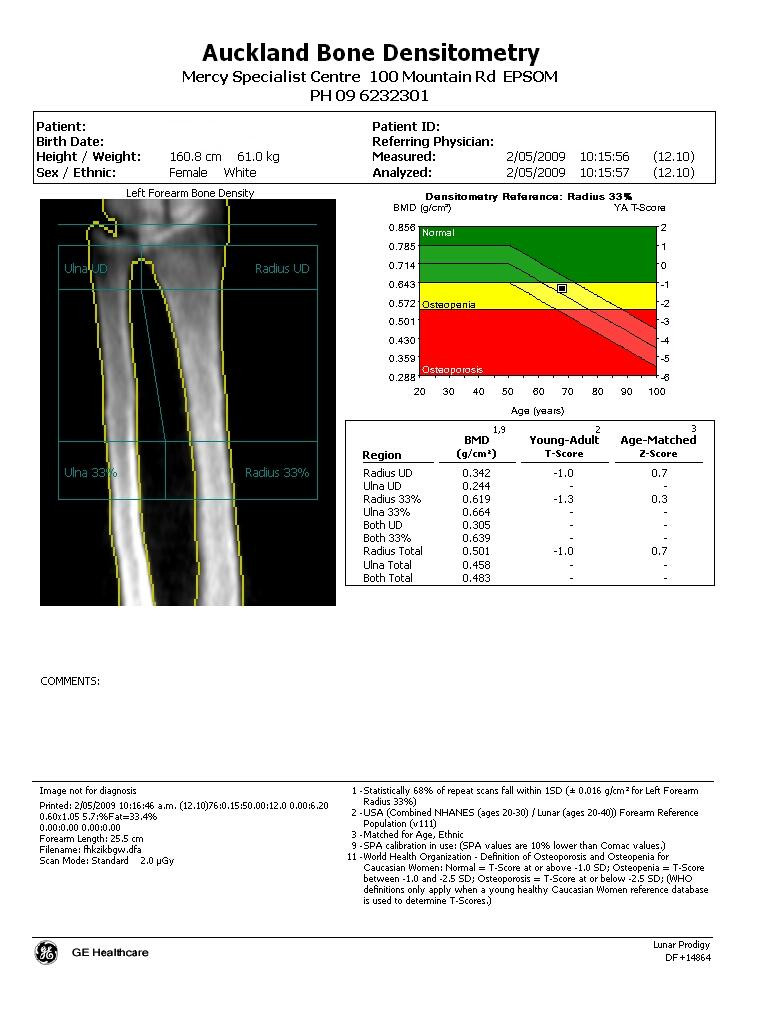

GE Healthcare bone density report sample

Bone Density Scan and chart of the forearm showing the ulna and radius Arm Bone Density Serota breaks down bone density testing, how to preserve your bone. At what age should you stop getting tested? It is a painless procedure that takes place at a hospital, medical clinic, or outpatient imaging center. What happens during a dexa scan? While you can’t do much to add to your bone mass in your later years, you can help. Arm Bone Density.

GE Healthcare bone density report sample Arm Bone Density Serota breaks down bone density testing, how to preserve your bone. While you can’t do much to add to your bone mass in your later years, you can help protect what’s left. A bone density test can help diagnose osteopenia and osteoporosis, which decrease bone density and strength, but does not show arthritis. These types of tests measure bone density. Arm Bone Density.